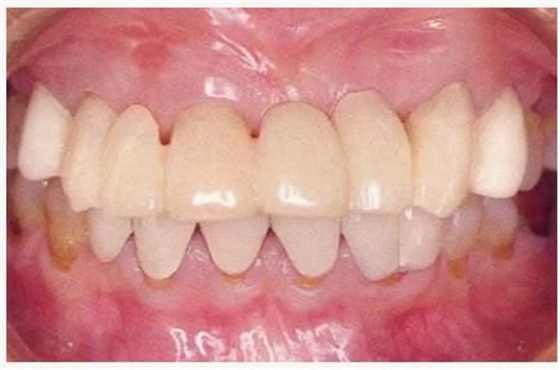

左上3到右上3的牙齒,通過(guò)包含牙槽骨外科處理在內(nèi)的APF進(jìn)行治療,確保了獲得biologic width所必需的、3mm以上的健全牙體組織。為獲得附著齦,使用FGG對(duì)左上4和右上4的牙齒進(jìn)行了治療。

圖6-9 牙周外科治療5個(gè)月后,最終取模前的狀態(tài)?;乐車@得了充足的附著齦。